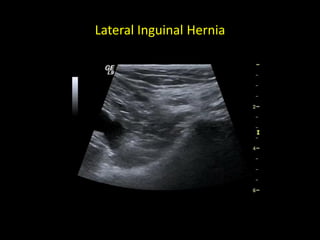

Lateral Inguinal Hernia

Indirect Hernia (Lateral Hernia)